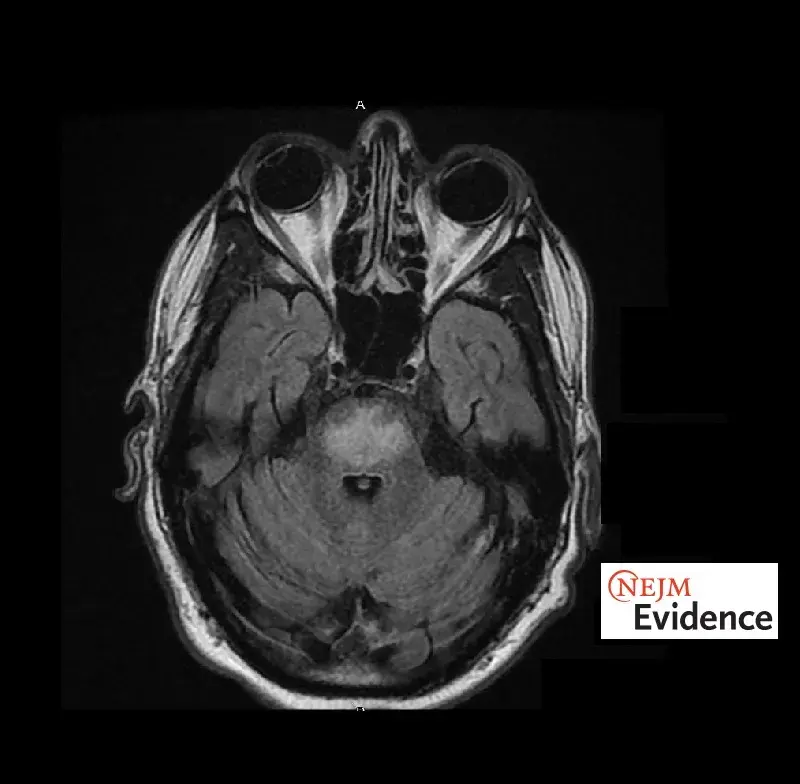

Síndrome de Desmielinización Osmótica: ¡Rara, pero potencialmente grave!